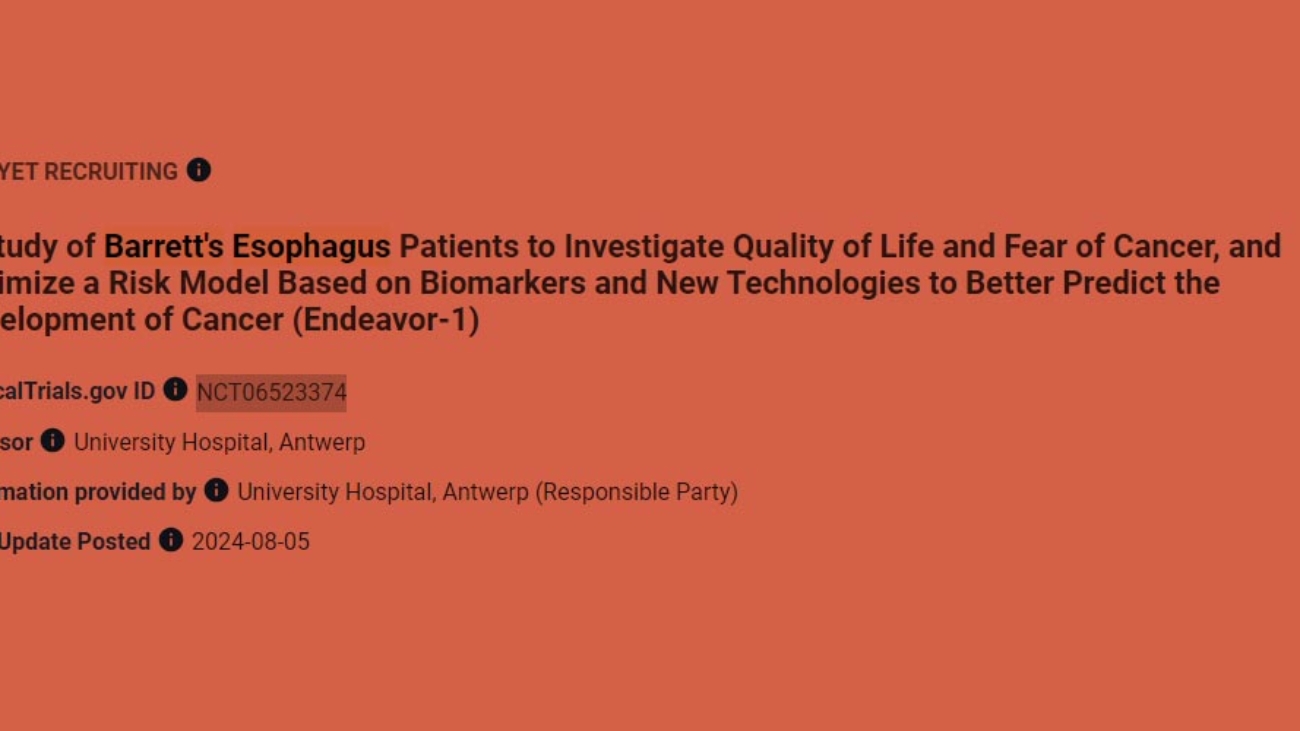

- The Endeavor study will consist of a pilot study to test the flow and afterwards a larger study (RCT). The meeting mainly focused on the current status of the pilot study (the status of ethics committee approval at all recruiting sites, the challenges that have occurred so far, the expected start date, the flow for taking and processing biological samples etc).

- In addition, several partners presented their plan of action for the conduct of the pilot study and the follow-up study, specifically for their part of the project.

- Also, we discussed the steps required for a smooth start of the follow-up RCT study.